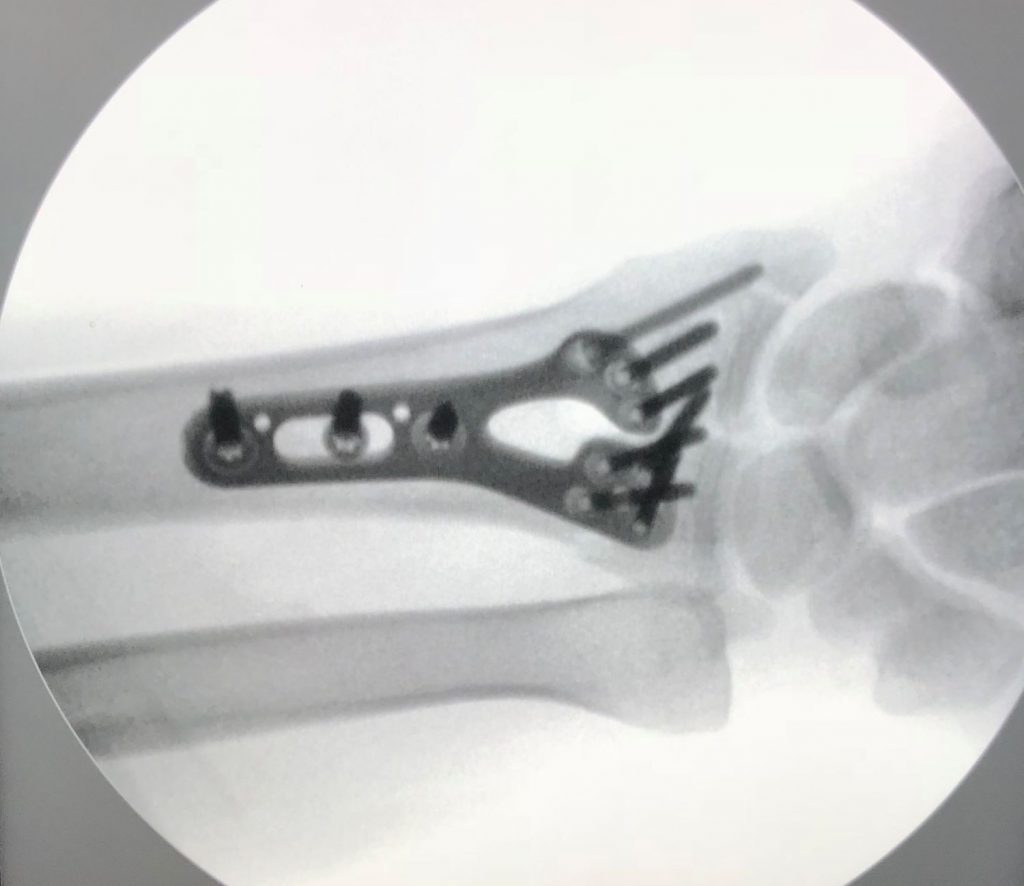

PATOLOGIAS MUÑECA - FRACTURAS DE LA MUÑECA Figura 2 - Fijación de fractura de muñeca con placa y tornillos.

Figura 2 - Fijación de fractura de muñeca con placa y tornillos.

Las fracturas se pueden fijar con muchos dispositivos (Figura 2). Se pueden usar clavos, tornillos, placas, varillas, agujas o fijación externa. Se podría usar una videocámara pequeña (Figura 3) para ayudar a visualizar la articulación desde el interior (Ver apartado de Artroscopia de Muñeca). A veces el hueso está tan dañado que después de realinearlo queda un espacio hueco. En esos casos, se podría añadir un injerto óseo para ayudar al proceso de consolidación. El Dr.Polo le informará de las mejores opciones para que sane y se recupere.